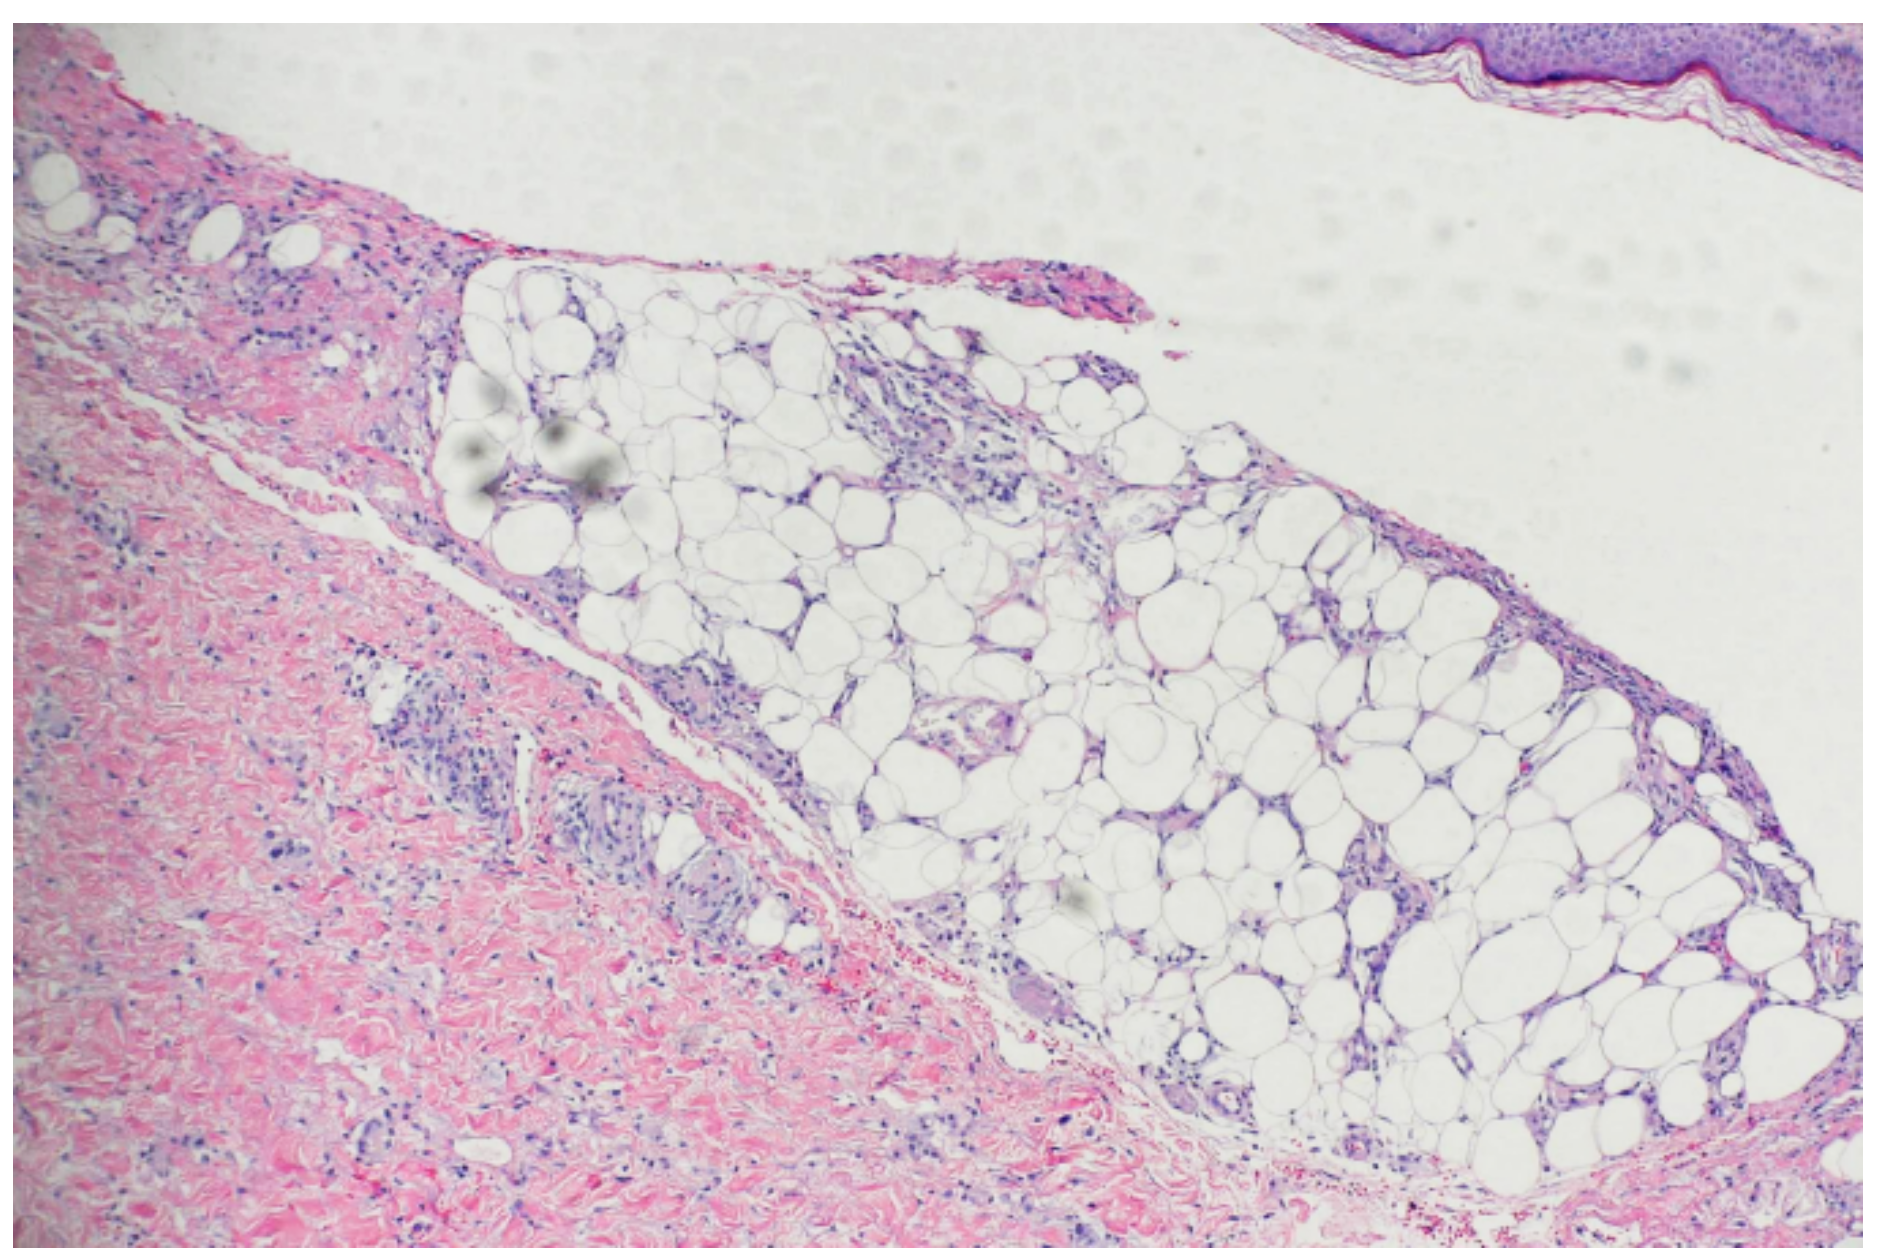

2. Case Presentation